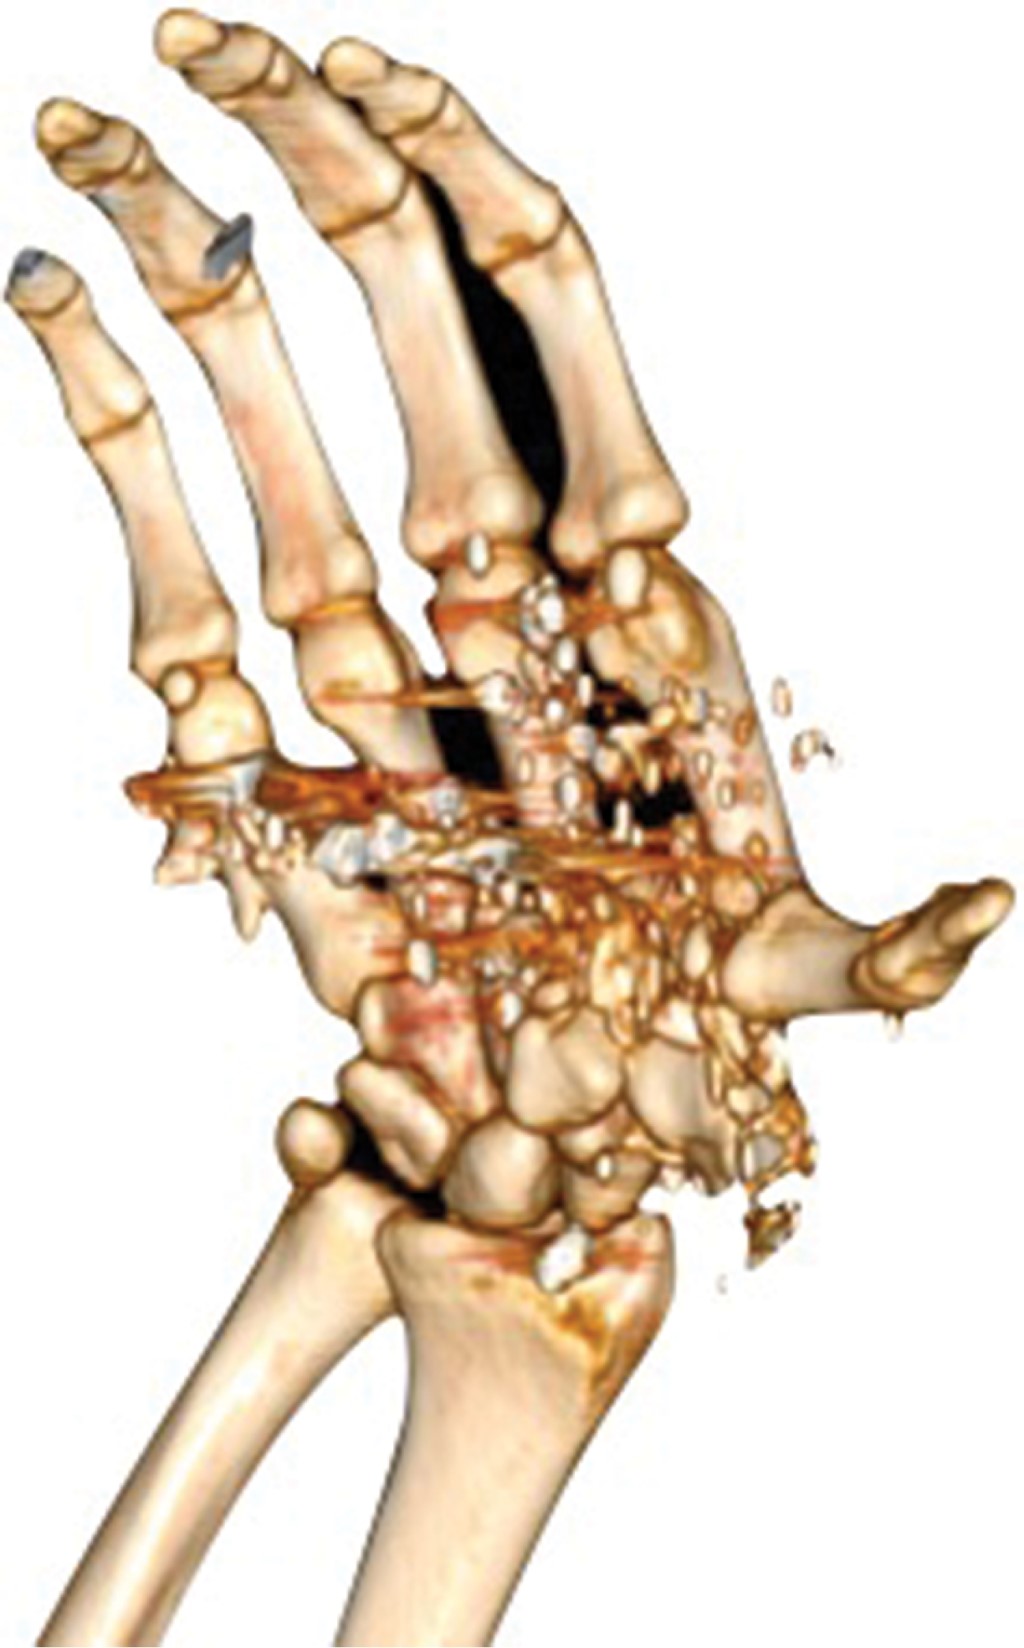

Free flaps for traumatic hand reconstruction due to gunshot injury; case report and literature review

Gunshot wounds cause about 15% of open fractures admitted in a hospital in border cities, up to half of these are serious injuries with a high incidence of skin and bone loss, and in severe cases with vascular damage. We report the case of a patient with traumatic hand injury secondary to a gunshot wound with a radial artery injury treated with a free radial contralateral forearm flap without success, subsequently an anterolateral thigh flap was performed with good outcomes for his social and labor reintegration.

Figure 1